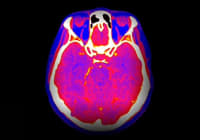

Sepsis remains a leading cause of morbidity and mortality, requiring rapid and precise intervention to improve patient outcomes. Early detection and management are critical, as delayed treatment can significantly increase the risk of progression to septic shock and multiple organ failure. Computed tomography (CT) is widely used to identify infectious foci, providing clinicians with essential diagnostic information that informs treatment decisions. However, the use of CT scans presents certain risks, including exposure to ionising radiation and potential adverse effects from iodinated contrast media administration. A recent interdisciplinary survey published in Insights into Imaging explored physicians' perspectives on the benefits and risks of CT in septic patients, offering insights into the factors influencing clinical decision-making across different medical specialities.

The survey revealed a strong consensus among physicians regarding the necessity of CT scans in sepsis management, with the majority agreeing that the benefits outweigh the associated risks. CT imaging enables the rapid identification of infection sources, such as pneumonia, intra-abdominal abscesses or other critical complications, which are essential for guiding appropriate treatment. Timely imaging is particularly important, given that delays in antimicrobial therapy and surgical intervention can lead to increased mortality rates in septic patients.